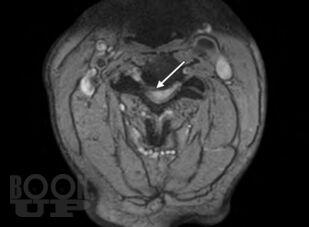

This is a unique atlas with contributions from international experts describing the most simple and advanced pain intervention techniques in a stepwise manner. The atlas provides a clear guide to identify the bony structures as seen on fluoroscopic examination enabling the operator to perform the spinal interventions safely. Remember: Bone is our Eye and Friend when performing spinal interventions under fluoroscopy. Chapters are consistently designedcovering indications, contraindications, equipment needed, and procedural stepswith the text presented in a bulleted style. Including several cases in some of the spinal intervention chapters will prepare the readers to overcome the challenges and the variability that are encountered in clinical practice. Some of the ultrasound-guided techniques described will enable readers to consider performing some pain-relief procedures in remote settings where fluoroscopy or CT guidance is not available.